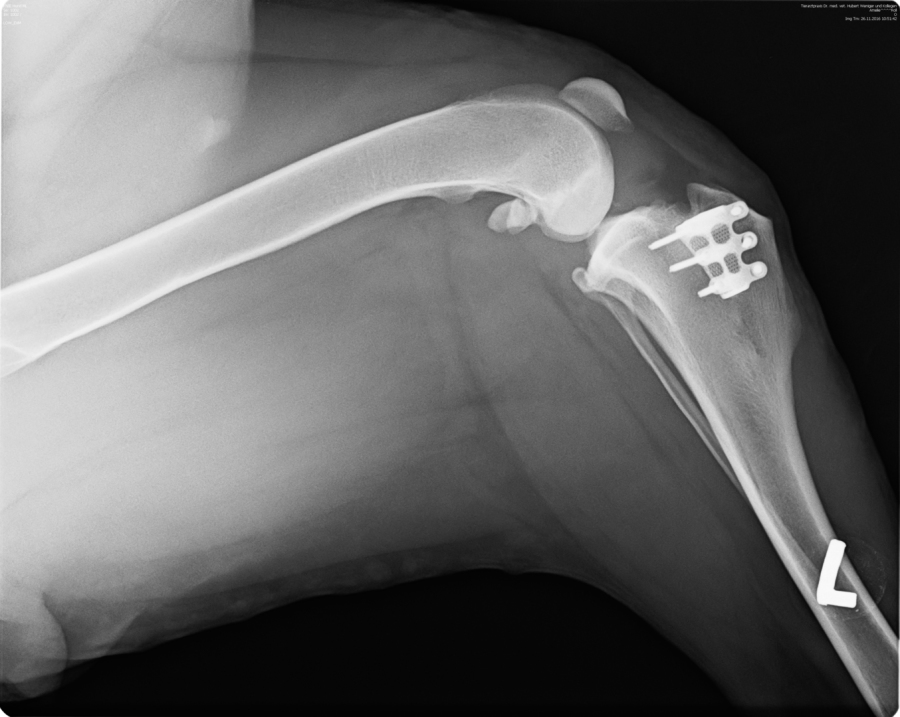

05.12.2016

Das Implantat, das die inneren Kreuzbänder ersetzt, ist gut in Amélies Kmochen eingewachsen. Man merkt, dass es ihr langsam besser geht, die "Renneinheiten" werden wieder länger und ausgedehnter!